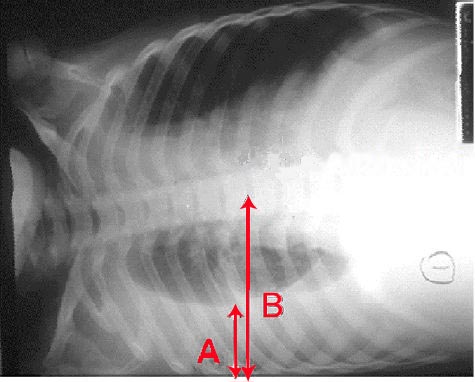

IVC Assessment

Scanning approach: Transverse (short axis) preferred over longitudinal - easier to assess size and collapsibility

Normal IVC: ~2 cm diameter, oval shape, respiratory variation

FindingSizeCollapsibilityInterpretationAction

DistendedRound, > 2.5 cmMinimal respiratory variationHigh CVP - likely obstructive/cardiogenicScan heart

CollapsingSlit-like <1 cmCollapses significantlyHypovolemiaGive fluids

Mid-rangeOval, ~2 cmModerate variationNon-contributoryClinical decision